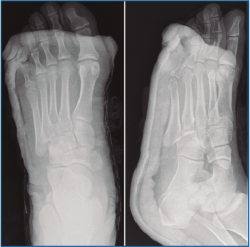

En la exploración destaca una inflamación y dolor en el borde externo del pie que no impide la deambulación. En la revisión de las pruebas complementarias (radiografía simple y TC) se confirman las lesiones previamente diagnosticadas, junto con una luxación del cuboides plantomedial (Figuras 1 y 2).

Figura 2. Imágenes de la tomografía computarizada (TC) que ponen en evidencia la fractura de la base del 4.º metatarsiano con la luxación plantar del cuboides.

Figura 6. Radiografía al mes de la cirugía con la correcta reducción ósea.